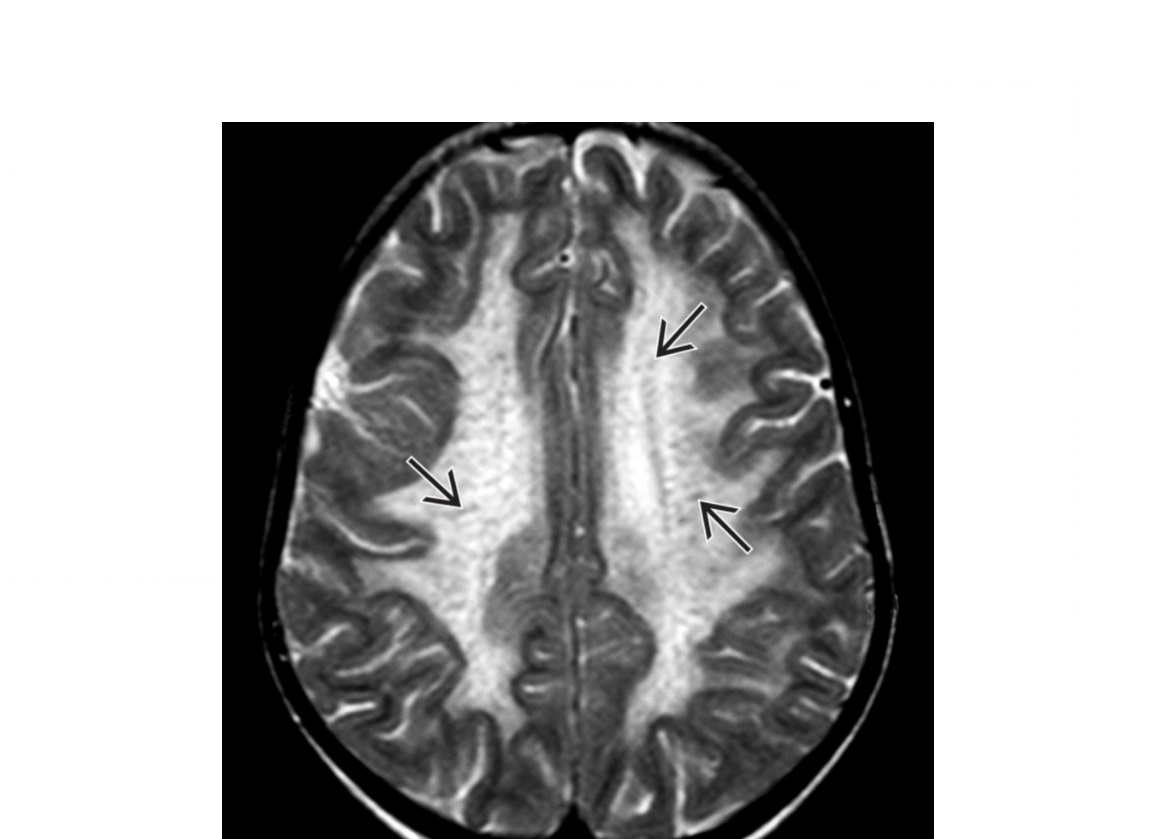

Demyelination with bilateral asymmetrical T2/FLAIR hyperintensities (confluent or punctuate).

Thalamic involvement and cranial nerves (not typcial MS)